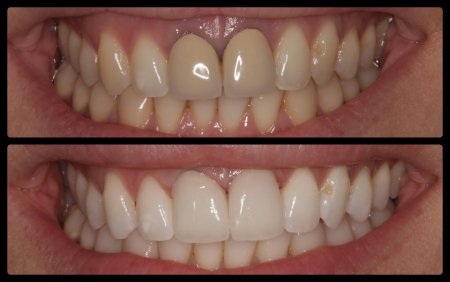

ΠΡΟΣΘΕΤΙΚΕΣ ΑΠΟΚΑΤΑΣΤΑΣΕΙΣ ΜΕ ΣΥΝΔΥΑΣΜΟ ΛΕΥΚΑΝΣΗΣ, ΣΥΝΘΕΤΩΝ ΡΗΤΙΝΩΝ ΚΑΙ ΟΛΟΚΕΡΑΜΙΚΩΝ ΟΨΕΩΝ ΚΑΙ ΣΤΕΦΑΝΩΝ